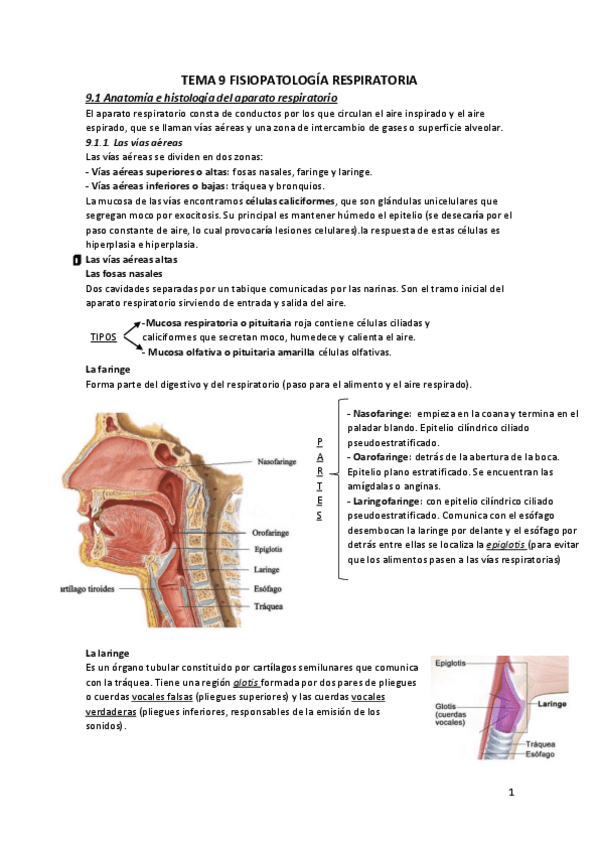

He publicado nuevos apuntes de Fisiopatología general: tema-9-aparato-respiratorio.pdf